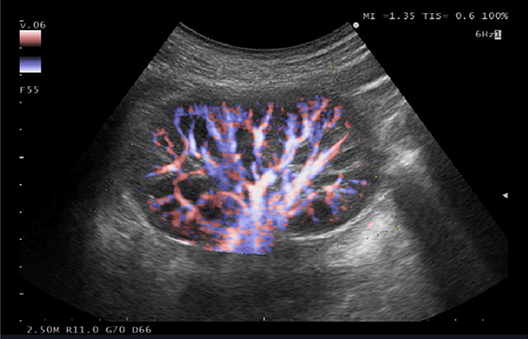

eFLOW is a flow mapping technology that enables accurate and detailed depiction of blood flow dynamics.

Its exceptional spatial resolution allows accurate delineation of both fine and larger blood vessels.